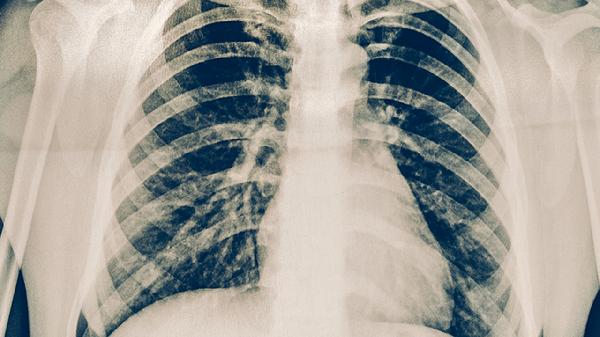

肺結(jié)核的護(hù)理措施主要有保持室內(nèi)通風(fēng)、規(guī)范用藥管理、加強(qiáng)營(yíng)養(yǎng)支持、隔離防護(hù)措施、定期復(fù)查監(jiān)測(cè)等。

治療期間每月需進(jìn)行痰涂片檢查和胸部X線復(fù)查,評(píng)估病灶吸收情況。同時(shí)監(jiān)測(cè)肝功能、血常規(guī)等指標(biāo),及時(shí)發(fā)現(xiàn)藥物性肝損傷等并發(fā)癥。完成療程后仍需隨訪,第一年每3個(gè)月復(fù)查,之后根據(jù)醫(yī)生建議調(diào)整復(fù)查頻率。